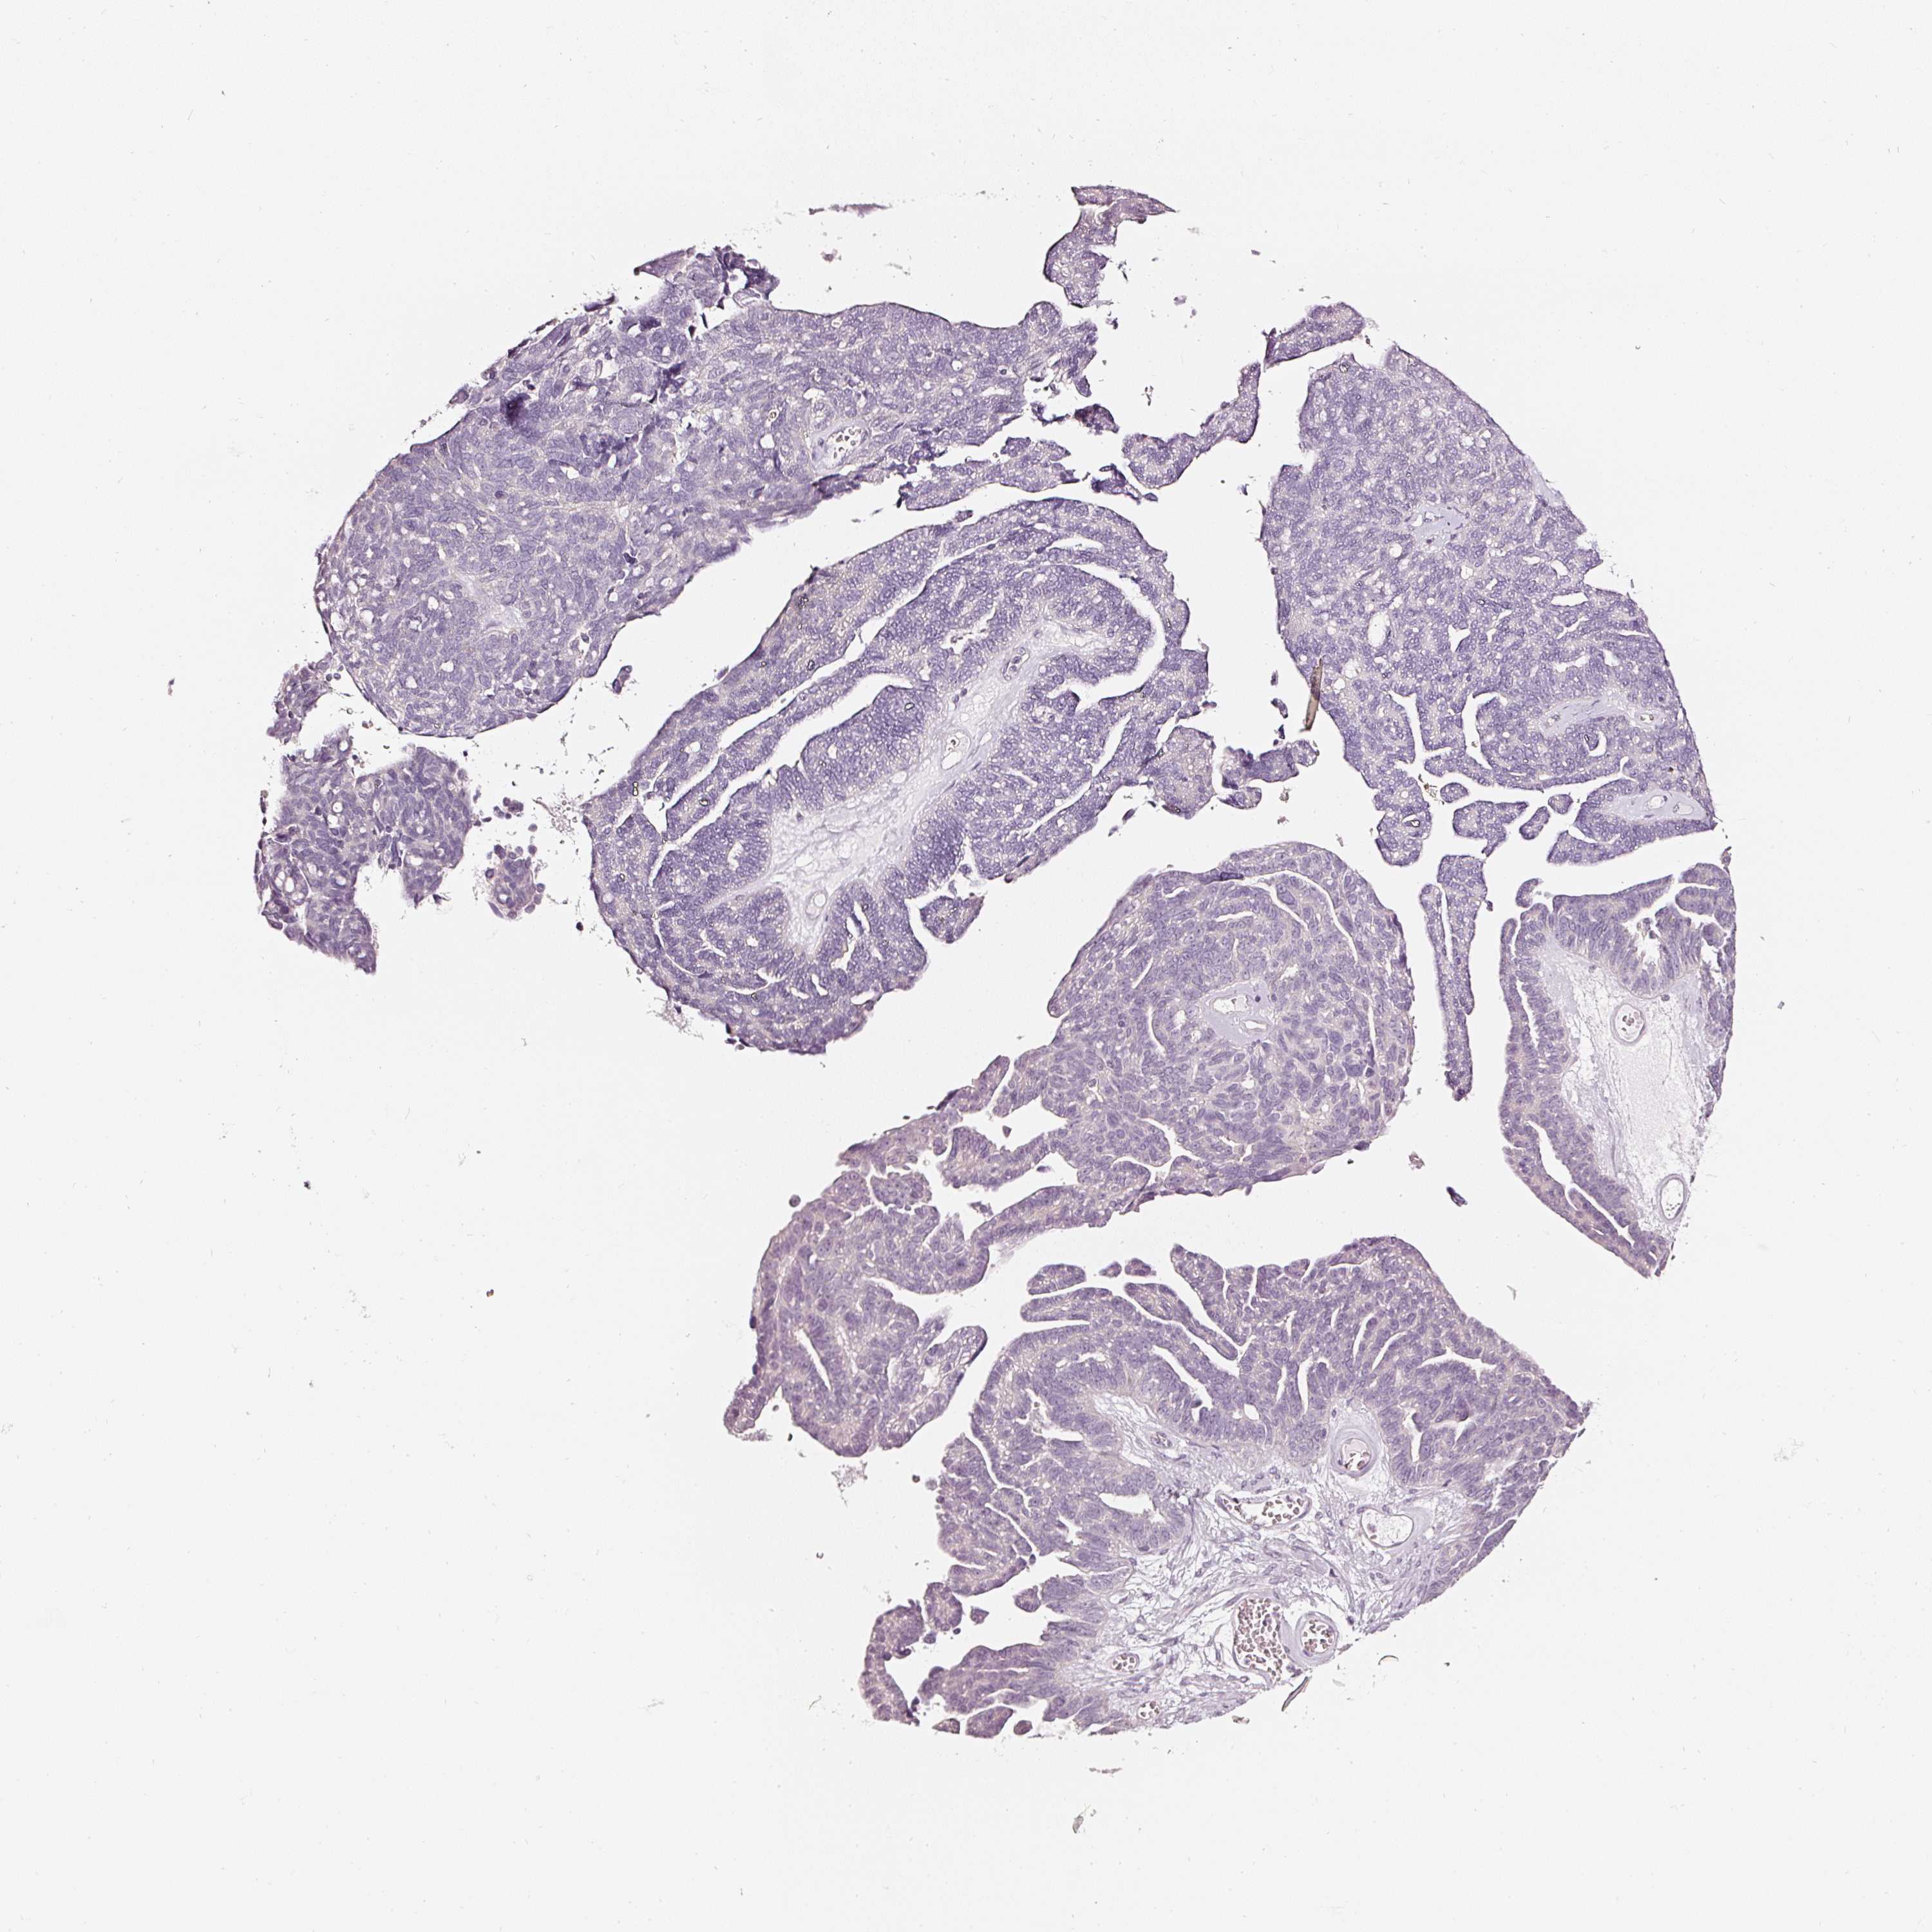

OVARIAN CANCER - Protein expressioni

A mouse-over function shows sample information and annotation data. Click on an image to view it in a full screen mode. Samples can be filtered based on level of antibody staining by selecting one or several of the following categories: high, medium, low and not detected. The assay and annotation is described here.

Note that samples used for immunohistochemistry by the Human Protein Atlas do not correspond to samples in the TCGA dataset.

Antibody stainingi

Antibody staining in the annotated cell types in the current human tissue is reported as not detected, low, medium, or high, based on conventional immunohistochemistry profiling in selected tissues. This score is based on the combination of the staining intensity and fraction of stained cells.

Each image is clickable and will lead to virtual microscopy that enables deeper exploration of all samples and also displays staining intensity scores, fraction scores and subcellular localization as well as patient and tissue information for each sample.

HPA023266

HPA023278

HPA023280

HPA023338

CAB002672

Cystadenocarcinoma, serous, NOS

Carcinoma, endometroid

Cystadenocarcinoma, mucinous, NOS

Carcinoma, NOS